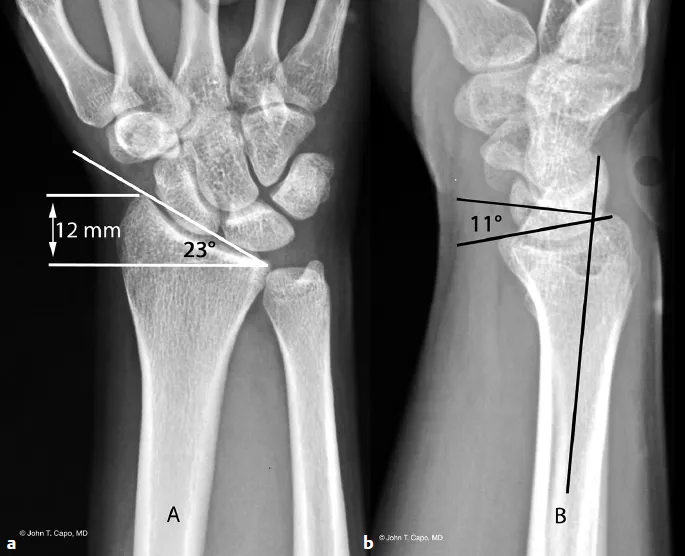

2. Thông số chụp X quang

Dưới đây là thông thườngy đã sử dụng các thuật ngữ chụp ảnh bức xạ và các định nghĩa ngắn được sử dụng để định lượng sự căn chỉnh hướng tâm ở xa.

Phương sai trụ: chiều dài tương đối của bề mặt khớp xa của xương trụ so với bán kính, được đo trên ảnh chụp X quang PA trung tính. Phương sai cực ảnh hưởng đến sự phân bổ tải trọng trên cổ tay.

Độ nghiêng của Volar (lòng bàn tay nghiêng): góc được hình thành trên ảnh chụp X quang bên thực giữa một đường vẽ dọc theo bề mặt khớp hướng tâm ở xa và một đường vuông góc với trục dọc của bán kính. Độ nghiêng mặt xoay bình thường là khoảng 10–15° (lòng bàn tay). Mất độ nghiêng mặt trong hoặc độ nghiêng lưng có ý nghĩa lâm sàng.

Chiều cao xuyên tâm (chiều dài xuyên tâm): được đo trên phim X quang PA là khoảng cách từ đầu của mỏm trâm quay đến góc trụ của bề mặt khớp bán kính xa (hoặc một tài liệu tham khảo nhất quán), thường ~11–12 mm ở người lớn bình thường.